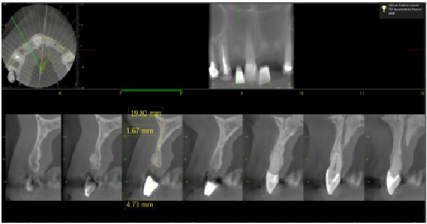

The patient is a 52-year-old female with a non-contributory medical history. The patient was missing teeth #s 7, 9 and 10 and she was interested in replacing these teeth with dental implants. A Cone Beam Computer Tomography (CBCT) of the maxillary arch was completed and reviewed with a clinical evaluation also (Figure 1, Figure 2, and Figure 3). Significant labial concavities and bone atrophy was noted and guided bone regeneration (GBR) was recommended using a d-PTFE, Cytoplast® titanium reinforced membrane (Osteogenics Biomedical, Lubbock, TX, USA).

Figure 2: Pre-operative CBCT of the #7 site showing deficient labial bone. (1.67 mm of bone width). View Figure 2

Figure 3: Pre-operative CBCT of the #s 9 and 10 sites showing deficient labial bone (less than 2 mm of bone width). The yellow arrow indicates the incisive canal, thus horizontal bone width is required for the subsequent implant to be placed and to avoid this vessel. View Figure 3